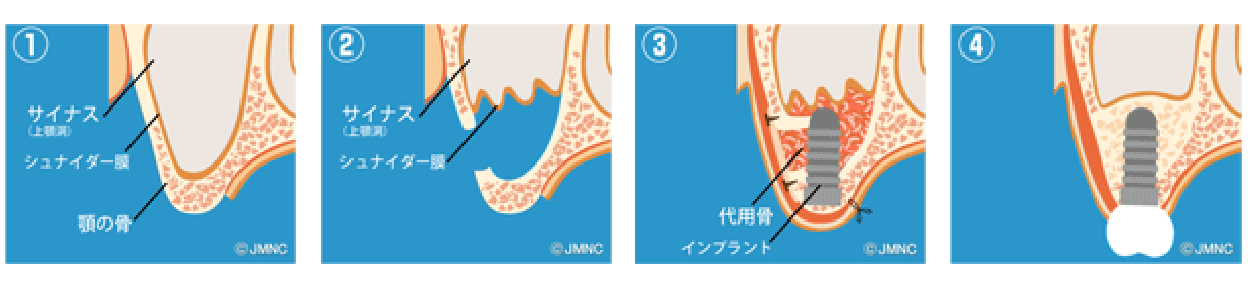

ソケットリフトとサイナスリフト

上顎臼歯部には上顎洞(副鼻腔の一つ)が存在し、骨の高さが足りない場合があります。その場合、上顎洞底部の洞粘膜(シュナイダー膜)を挙上し、挙上によってできた空隙に骨移植を行い骨造成し、インプラントが埋入できるようにします。当院では骨の高さが5~6mm以上の場合にソケットリフト、5~6mm未満の場合にサイナスリフトを行います。つまり、たくさんの骨移植が必要な場合にはサイナスリフトになります。